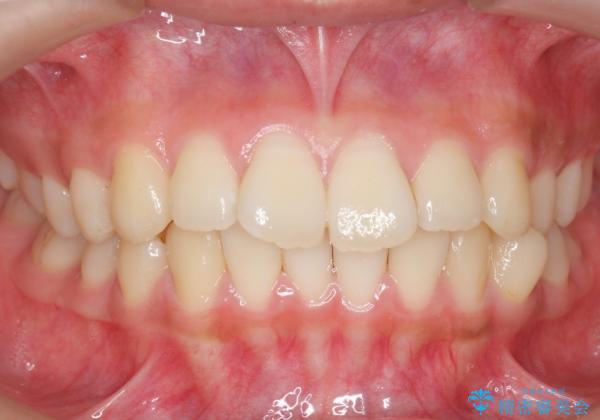

前歯のがたつき 部分矯正でコストダウンしながら、かみ合わせも治療

- 前歯のがたつきを気にして来院。

左下の小臼歯が捻転し、反対咬合になっていました。

先にワイヤーで部分矯正を行ってから、インビザラインの部分矯正を行いました。

先に難しい部分をワイヤー矯正することで、インビザラインの部分矯正コースで短期間で予算も抑えて確実に治すことができます。

専門的な話になりますが、下顎の小臼歯は円柱状の形をしており、インビザライン単独では捻転はほぼ治りません。

今回は左下の小臼歯が捻転が強く、そこが反対咬合になっていたため事前に部分矯正を行いました。